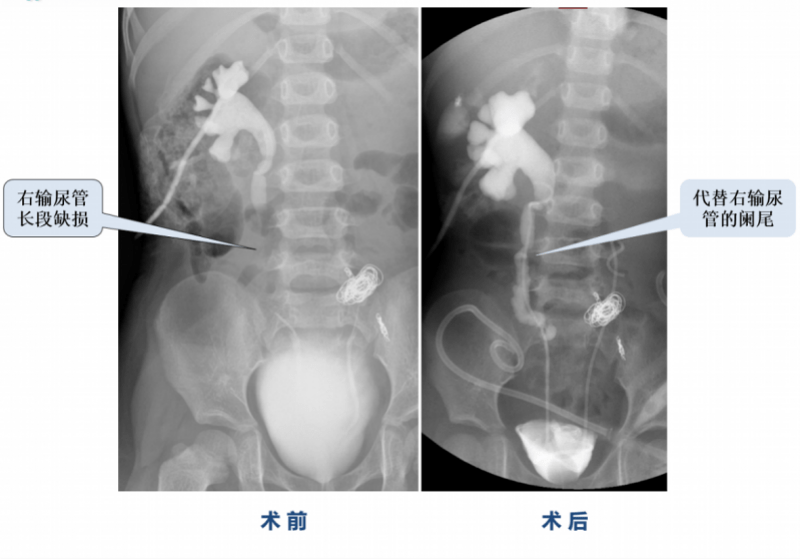

图说:术前术后的对比 。